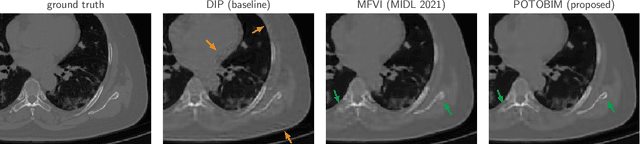

Abstract:We present Posterior Temperature Optimized Bayesian Inverse Models (POTOBIM), an unsupervised Bayesian approach to inverse problems in medical imaging using mean-field variational inference with a fully tempered posterior. Bayesian methods exhibit useful properties for approaching inverse tasks, such as tomographic reconstruction or image denoising. A suitable prior distribution introduces regularization, which is needed to solve the ill-posed problem and reduces overfitting the data. In practice, however, this often results in a suboptimal posterior temperature, and the full potential of the Bayesian approach is not being exploited. In POTOBIM, we optimize both the parameters of the prior distribution and the posterior temperature with respect to reconstruction accuracy using Bayesian optimization with Gaussian process regression. Our method is extensively evaluated on four different inverse tasks on a variety of modalities with images from public data sets and we demonstrate that an optimized posterior temperature outperforms both non-Bayesian and Bayesian approaches without temperature optimization. The use of an optimized prior distribution and posterior temperature leads to improved accuracy and uncertainty estimation and we show that it is sufficient to find these hyperparameters per task domain. Well-tempered posteriors yield calibrated uncertainty, which increases the reliability in the predictions. Our source code is publicly available at github.com/Cardio-AI/mfvi-dip-mia.

Abstract:Cold posteriors have been reported to perform better in practice in the context of Bayesian deep learning (Wenzel et al., 2020). In variational inference, it is common to employ only a partially tempered posterior by scaling the complexity term in the log-evidence lower bound (ELBO). In this work, we optimize the ELBO for a fully tempered posterior in mean-field variational inference and use Bayesian optimization to automatically find the optimal posterior temperature and prior scale. Choosing an appropriate posterior temperature leads to better predictive performance and improved uncertainty calibration, which we demonstrate for the task of denoising medical X-ray images.